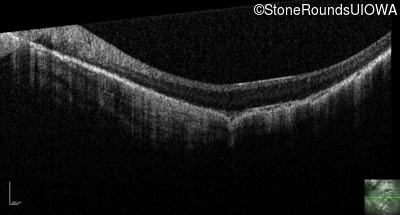

Optical Coherence Tomography - Right - 20/200 -1

Exemplar / OCT Stack